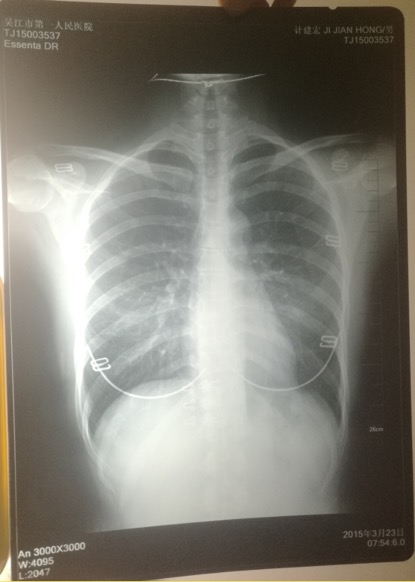

印有計(jì)建宏姓名的胸片實(shí)為一名女性的。 受訪者供圖

印著父親姓名的胸片,圖像卻顯示有明顯女性文胸搭扣和項(xiàng)鏈的印記。

“當(dāng)時(shí)我和母親都奇怪,一年多前體檢正常,怎么這么快腫瘤長(zhǎng)得如此大了?”更令計(jì)云強(qiáng)疑惑的是,該院胸外科主任在系統(tǒng)中輸入計(jì)建宏姓名后,查詢得到的胸片,可明顯看出有女性文胸的搭扣和項(xiàng)鏈,“后來醫(yī)生含糊地說可能是同名同姓,便不讓我看了。”

“7月初,我們回到吳江,帶著滿心悲傷和疑慮去了體檢科,想搞清楚父親的胸片究竟是怎么回事。”計(jì)云強(qiáng)稱,此后幾經(jīng)周折,在找了吳江區(qū)第一人民醫(yī)院體檢科、投訴科等多個(gè)部門后,耗時(shí)多月,才被體檢科通知去拿父親的胸片,“一張是我父親的名字,但有文胸印記;另一張是醫(yī)院所謂的我父親的胸片,顯示的是其他人的姓名。”